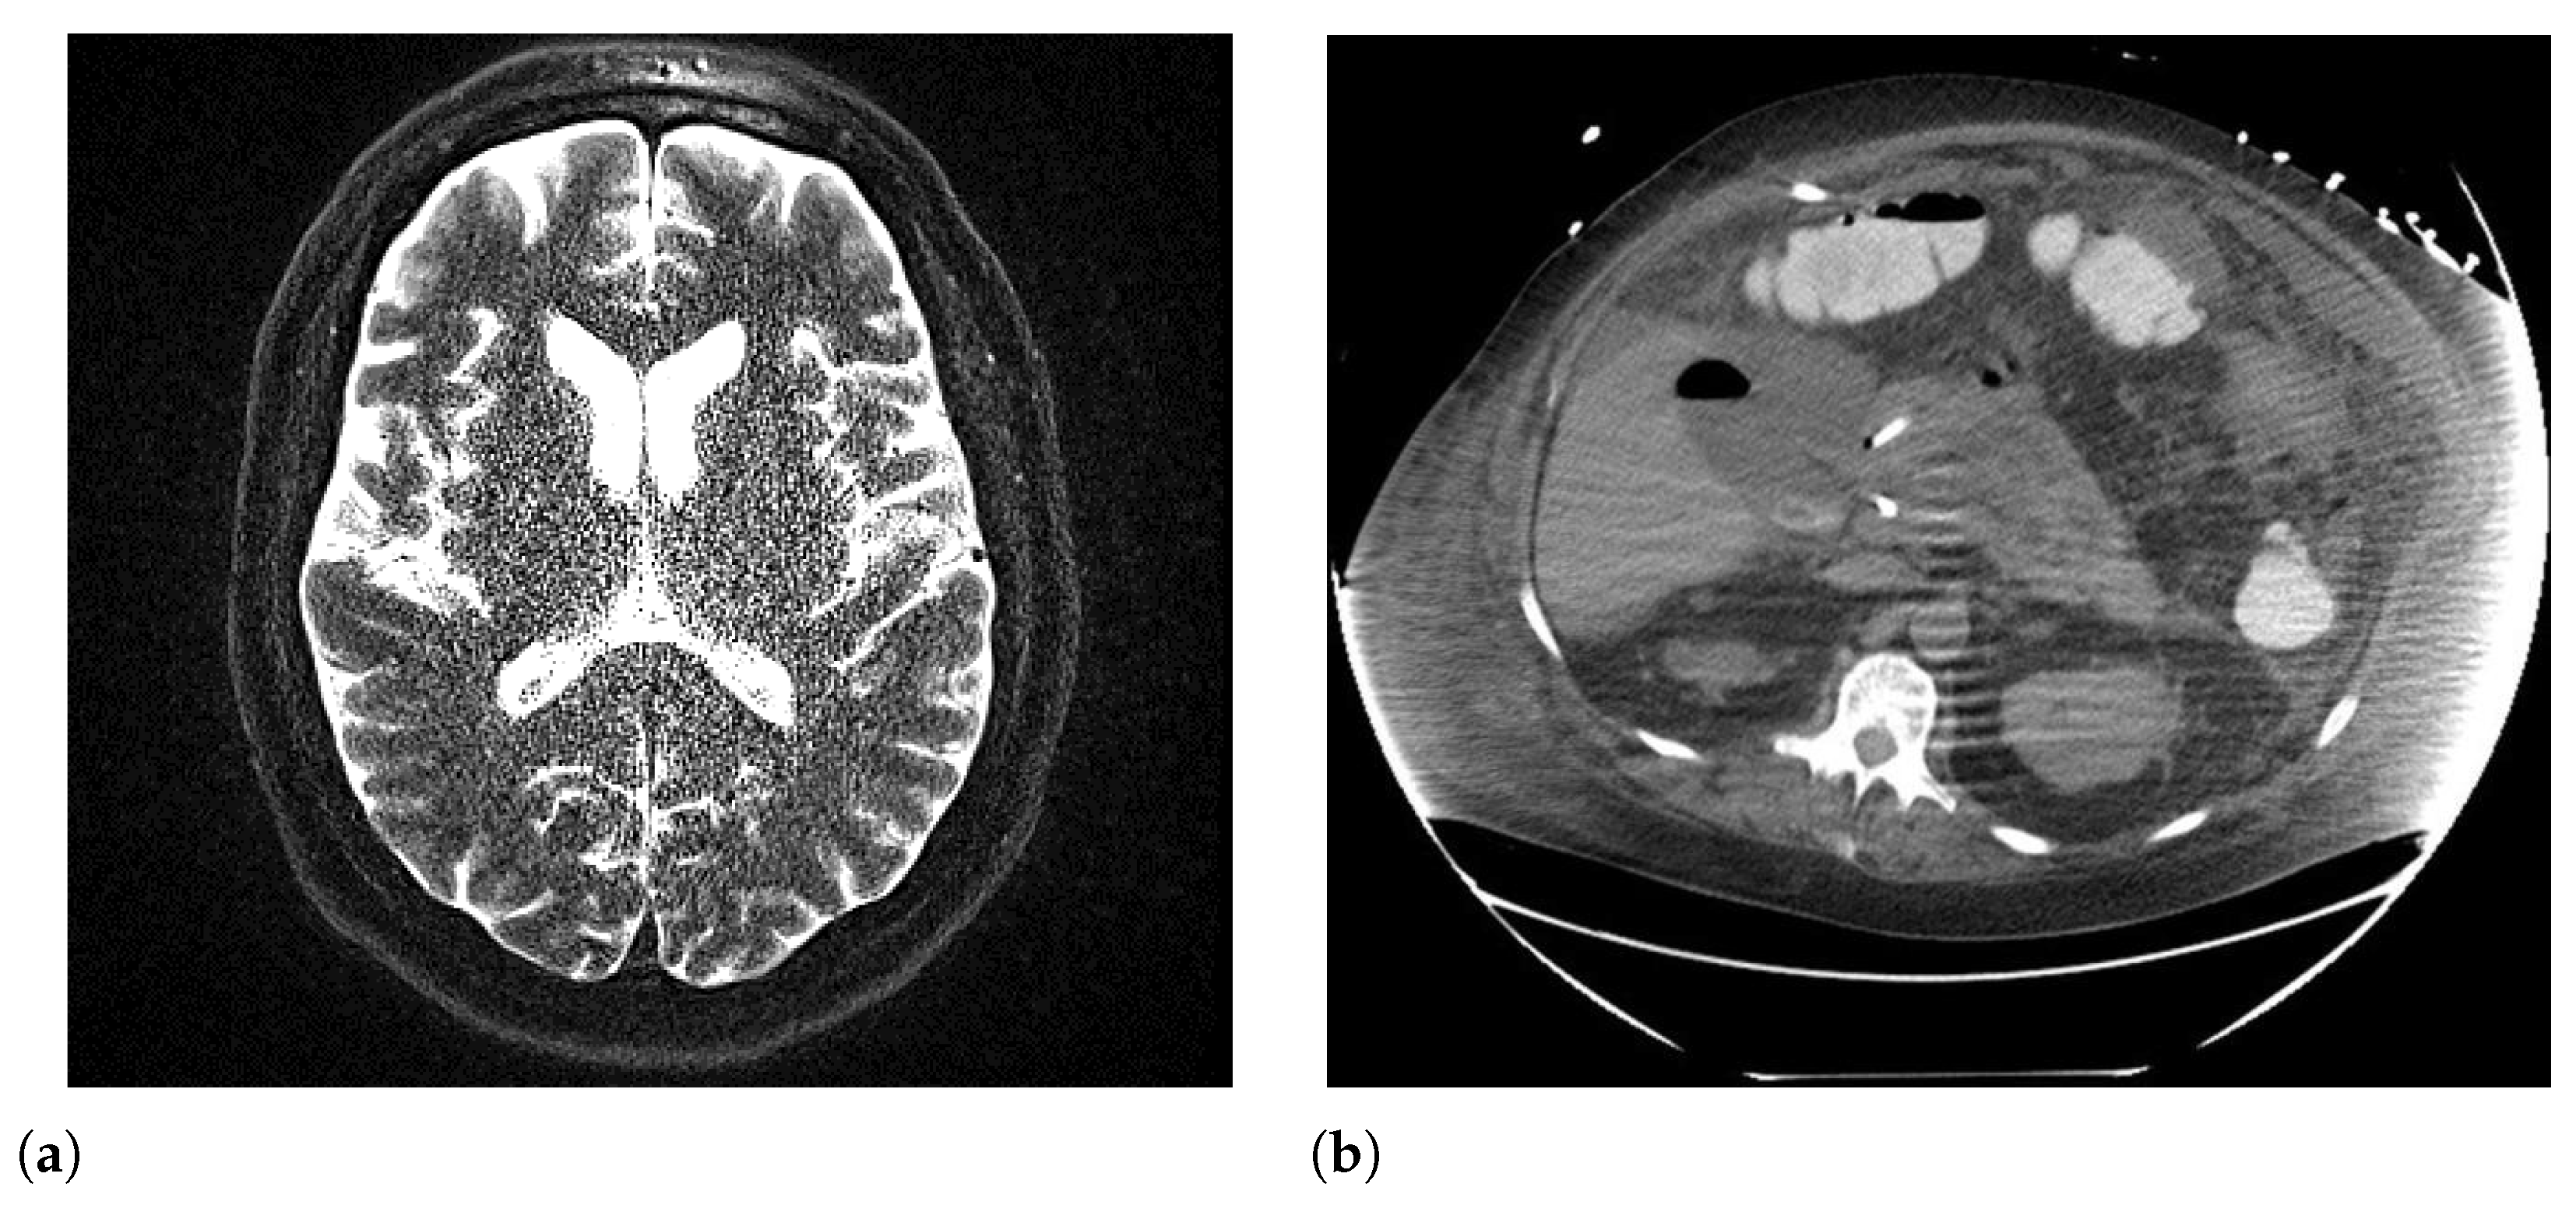

6.3. Noise

6.4. Blur

| Noise | CT, MRI, PET | Texture (GLCM, GLSZM), first-order | Increased variance, instability |

| Blur | CT, MRI, PET | Texture, shape | Loss of edge definition, misclassification |